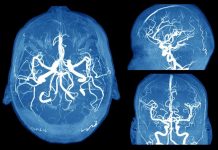

6 Scary Signs of a Brain Aneurysm Everyone Should Know

A brain aneurysm is a bulge in a blood vessel in the brain, according to the Mayo Clinic. It’s been described as looking like...